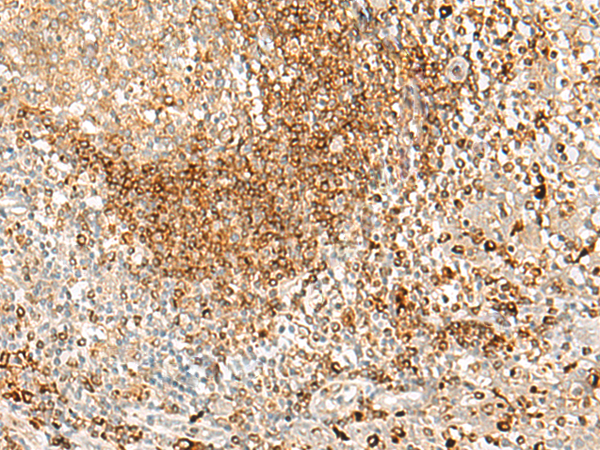

分类: 科研抗体货号: P06694别名: DOB; HLA_DOB应用: WB,IHC反应种属: Human